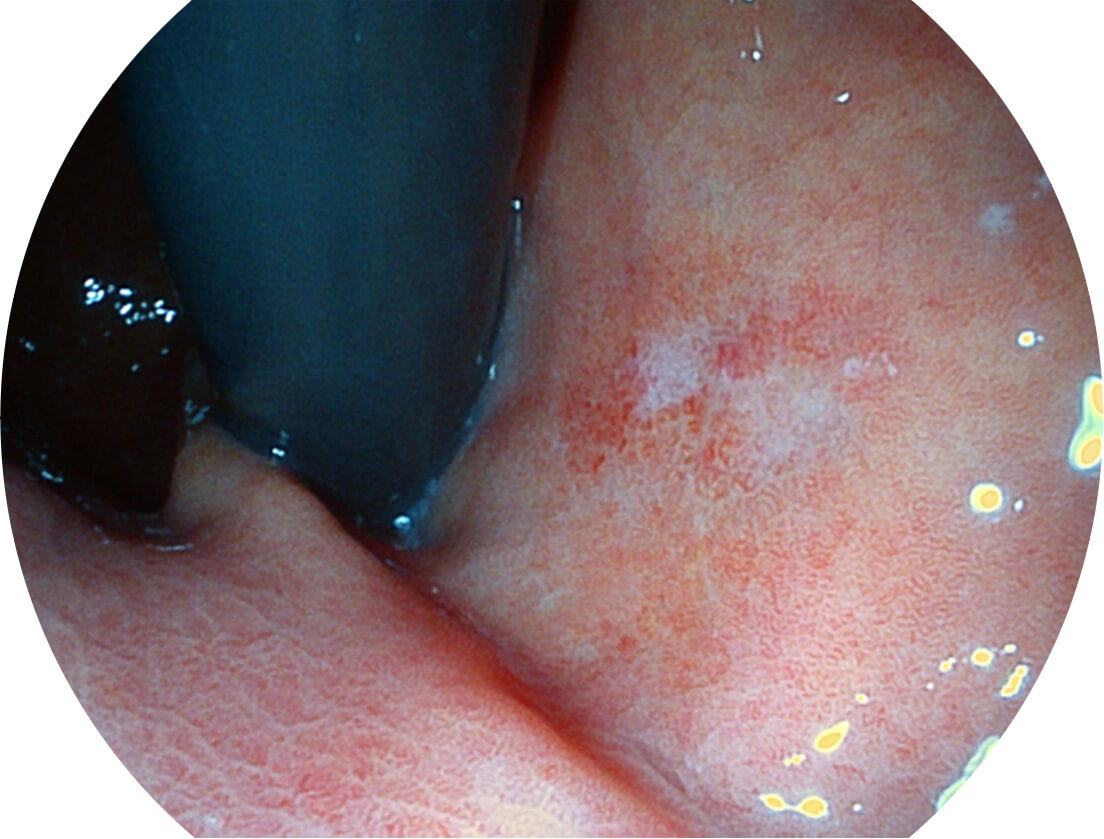

图像具有高亮度、高黏膜血管颜色对比度的特点,且不改变粘液、食物残渣、粪便的基本颜色,可在中远景下进行观察,助力消化道早期疾病的诊断。

• 白光图像 SFI图像